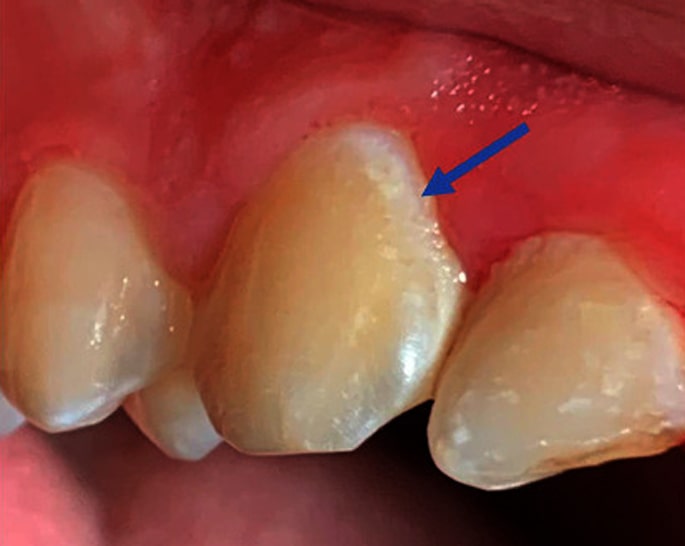

Раннее кариозное поражение проявляется как белое меловидное пятно на эмали. Это участок, где эмаль теряет минералы, но её поверхность остаётся целой, что позволяет лечить поражение без сверления. Белое пятно становится заметнее, когда зуб сухой: воздух в порах изменяет прохождение света и подчёркивает границу поражения. Поэтому стоматолог всегда сушит участок перед осмотром.

Белые пятна особенно часто появляются вокруг брекетов из-за сложности гигиены.